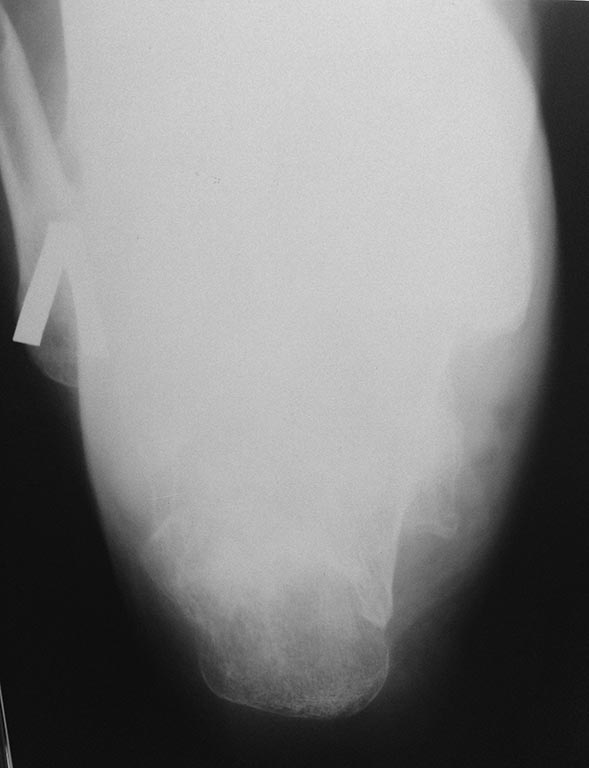

Поступил пациент 1947 г.р. Травма в январе 2014. Лечение консервативное - правая голень 1,5 месяца на ССВ, затем циркулярная гипсовая повязка; гипсовая лонгета на пятку, репозиции не было.Планируем оперировать,помогите с тактикой

Судя по снимку, пятка срослась и анкилоз в подтаранном суставе состоялся. Про жалобы и локальный статус Вы ничего не пишете. А если ориентироваться только на снимок, то со стопой делать сейчас ничего не нужно. Когда начнет наступать на нее можно будет подобрать комфортную (ортопедическую?) обувь и, вероятно, индивидуальную стельку. Или подпяточник. А на голени перелом позволяет применить любой способ фиксации на Ваше усмотрение. Опять же, с учетом локального статуса (качество кожного покрова, гнется ли колено и т.д.)

голень сломана справа, а пятка слева. пациент ходит на костылях с опорой на левую ногу, правая в циркулярной гипсовой повязке. активных жалоб не предъявляет. доступны и пластины и гвозди

Полагаю,необходимо проводить коррегирующий пяточно - таранный артродез для восстановления пяточно - таранных взаимоотношений, в случае, если позволяет состояние мягких тканей. В случае с голенью целесообразен БИОС пластиной с подъёмом импренированной части мыщелка.

Думаю, что на фоне перелома костей голени в проксимальной и средней трети перелом пяточной кости на данный момент меркнет. Корригирующую остеотомию можно и отложить и вернуться после лечения перелома голени - восстановление оси, длины и ротации в аппарате с последующей сменой фиксатора на внутри костный, дообследование мыщелков большеберцовой кости, их синтез. А пятка в конце этого пути.